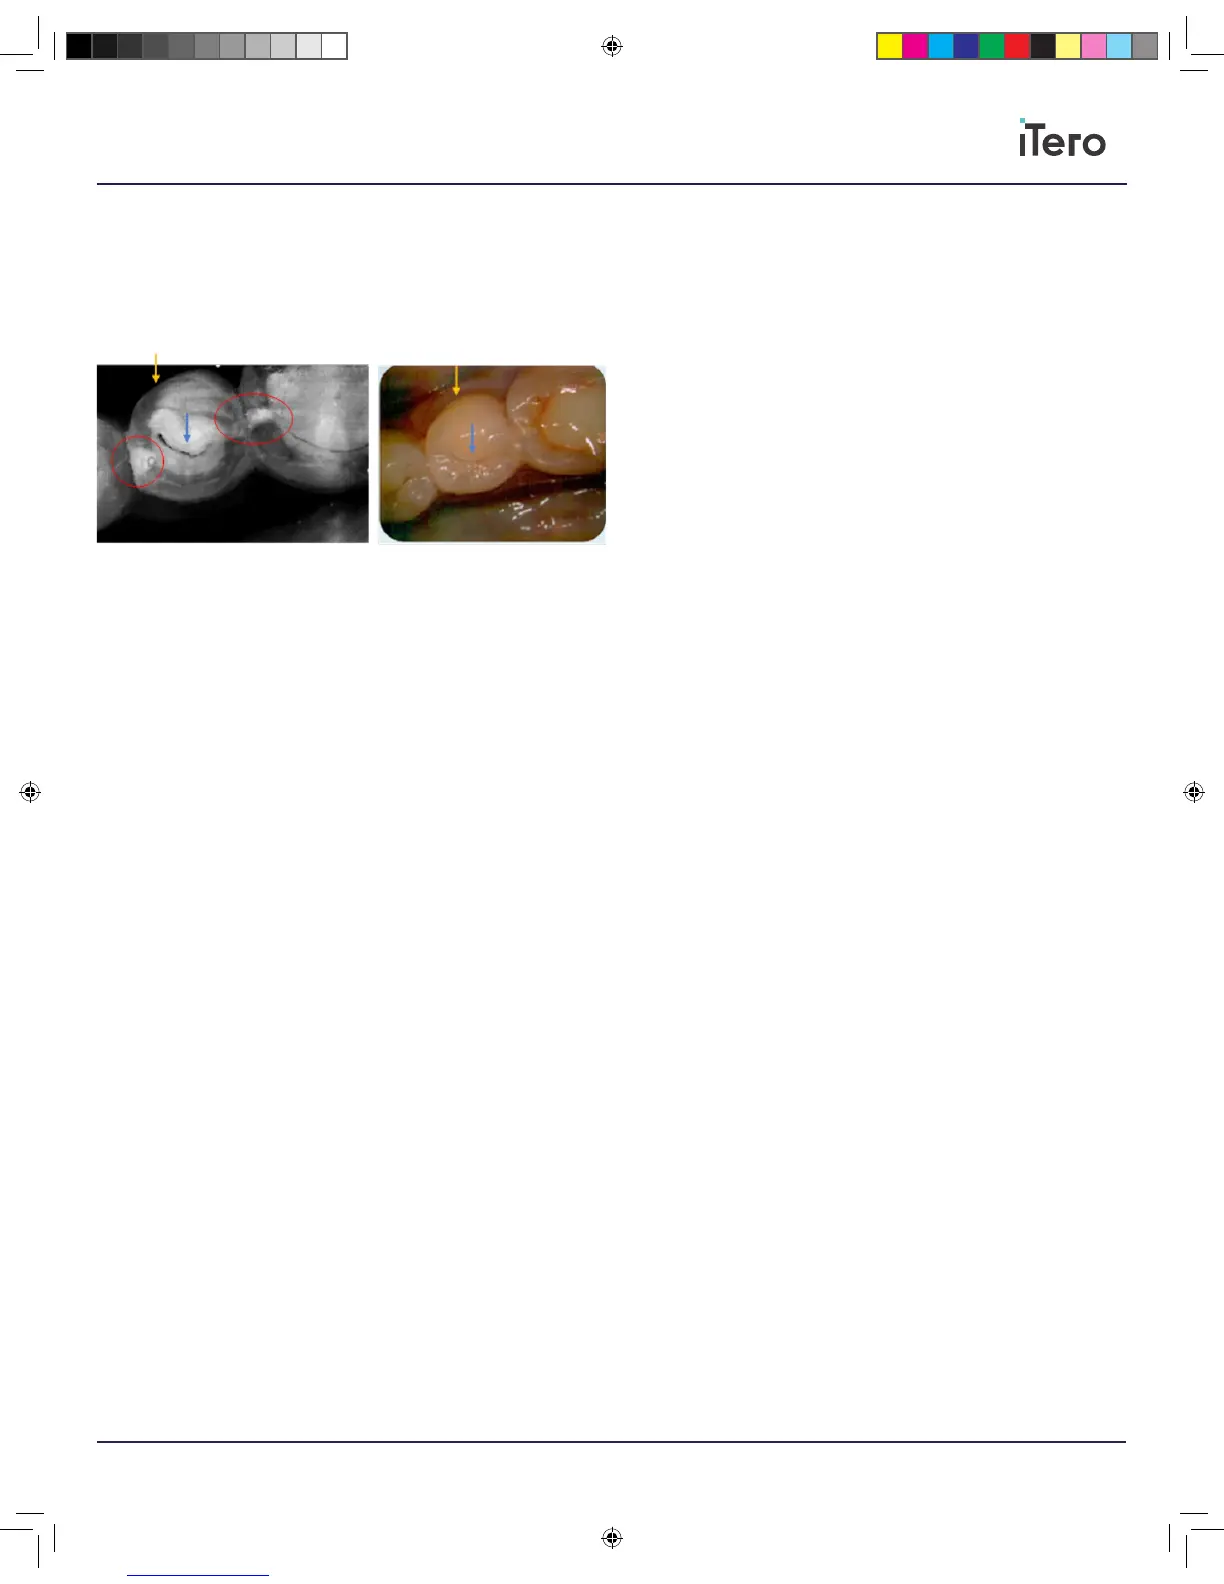

The NIRI above demonstrates two proximal lesions circled in red,

reaching all the way to the dentin, while the color image helps determine

that the lesions are proximal and not occlusal, as no white/brown spots

appear in the correlating areas of the occlusal surface in the color image.

The dark lines marked by the blue arrows indicate occlusal fissures.